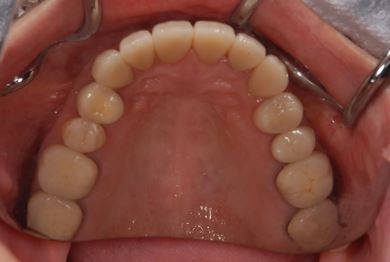

| 性別/年齢 | 女性 / 51歳 | ||||||||||||||||||||||||||||||||

| 主訴 | 前の歯の治療後の変色が気になる。詰め物がとれた箇所あり。痛みあり。 | ||||||||||||||||||||||||||||||||

| 治療方針 | セラミック治療にて、審美的回復を行う。 | ||||||||||||||||||||||||||||||||

| 治療内容 | オールセラミッククラウン7本(オールセラミック用土台1本)、ハイブリッドセラミッククラウン10本(ハイブリッドセラミック用土台9本)、ハイブリッドセラミックインレー1本 | ||||||||||||||||||||||||||||||||

| 総治療費 | 961,800円 | ||||||||||||||||||||||||||||||||

| 治療期間 | 10ヶ月 |